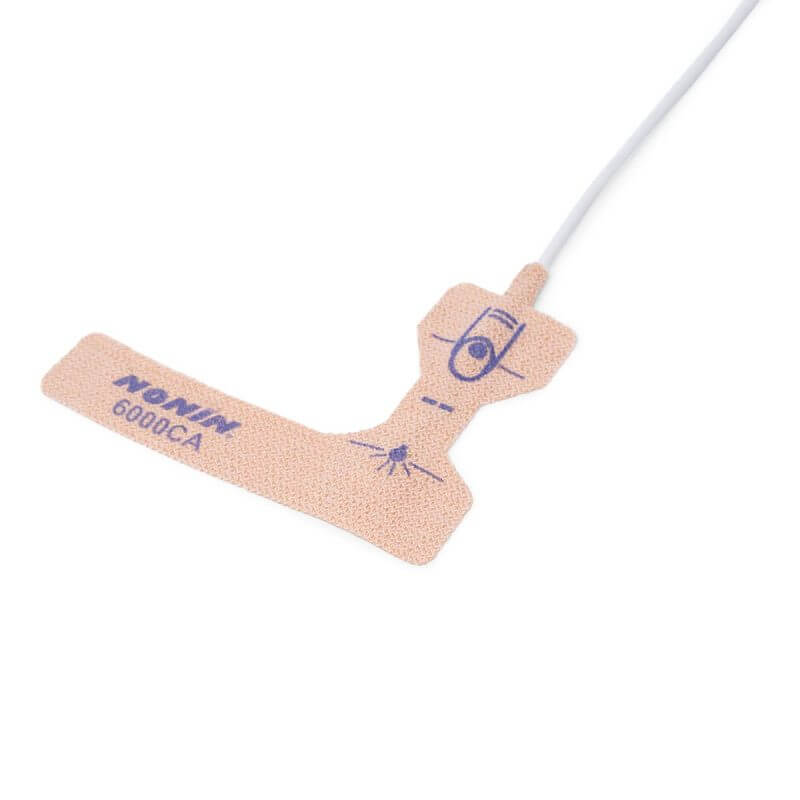

- Easy to Use Illustrated finger guide ensures easy and accurate placement by caregiver or patient

- Patient Friendly Not made with natural latex rubber

- Special Adhesive Allows the sensor to be repositioned multiple times as needed